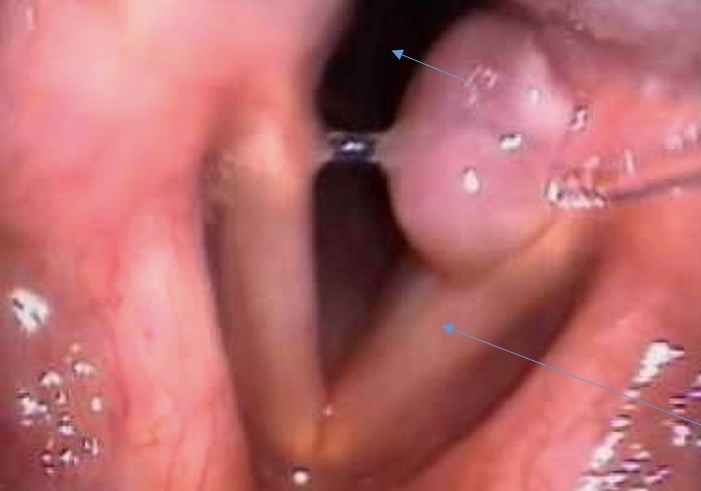

Vous pratiquez cet examen pour étayer votre hypothèse diagnostique. Vous mettez en effet en évidence un granulome sur une corde vocale constituant une laryngite de contact prolongé à la sonde d’intubation

Question 12 : Quelles sont les propositions vraies ?

La trachée

Le plan glottique = les cordes vocales

Car c’est inversé

On peut dire qu’il s’agit d’une nasofibroscopie souple car on la pratique par les fosses nasales ; l’avant est situé donc en arrière de notre vision en fibroscopie et inversement. Ici, les cordes vocales forment un V. La pointe du V étant vers l’avant, on a donc des rapports inversés à une endoscopie rigide (où l’avant est en avant, et l’arrière en arrière).

Le granulome est ici post-traumatique : probablement l’intubation a dû blesser la corde vocale gauche et créer une réaction granulomateuse de contact.

Le granulome est classiquement postérieur. Il est soit secondaire à un traumatisme, soit secondaire au reflux gastro-œsophagien